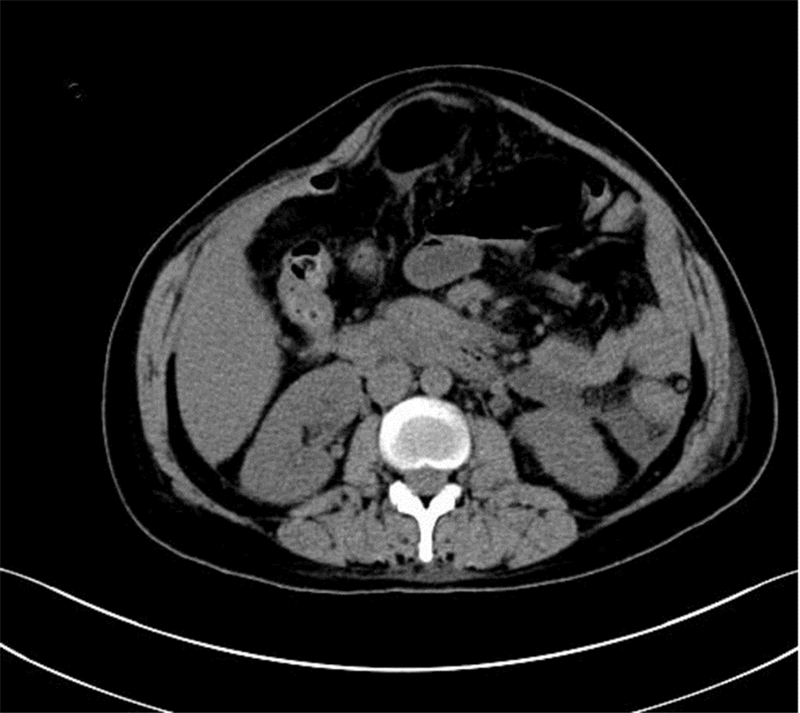

患者于入院10 h前进食后突发上腹部疼痛,呈持续性刀割样剧痛,伴腹胀,恶心、呕吐,呕吐物为胃内容物,无呕血、黑便,无腰背放射痛,无发热、寒战。在当地医院就诊,查血淀粉酶348 U/L,尿淀粉酶4 082 U/L,腹部CT示:“胰腺周围渗液,水肿,腹腔少量积液”(图 1),诊断考虑“急性胰腺炎”。入院查体患者痛苦貌,双肺呼吸音粗,可闻及干湿性啰音及散在湿啰音。窦性心动过速,心率101次/min,心律规整,各瓣膜听诊区未闻及病理性杂音。腹部膨隆,未见胃肠型。腹壁张力大,压痛明显,宫底触诊不清,胎心140次/min,宫缩不规律。肠鸣音减低。2014年5月12日抽血化验时发现患者严重脂血(图 2),积极给予患者抑制胰液分泌、抑酸、支持等对症支持治疗。诊断考虑高甘油三酯血症急性胰腺炎(HTGP),同时给予特异性治疗:低分子肝素钙4 100 U皮下注射 q12 h,非诺贝特 0.1 口服q8 h。

| 图 1 患者2014年5月11日腹部CT图像 |